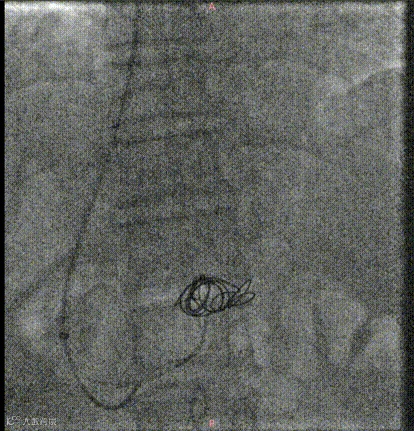

经右颈内静脉穿刺门静脉右支后行造影

超选择插入至曲张静脉,注入弹簧圈栓塞